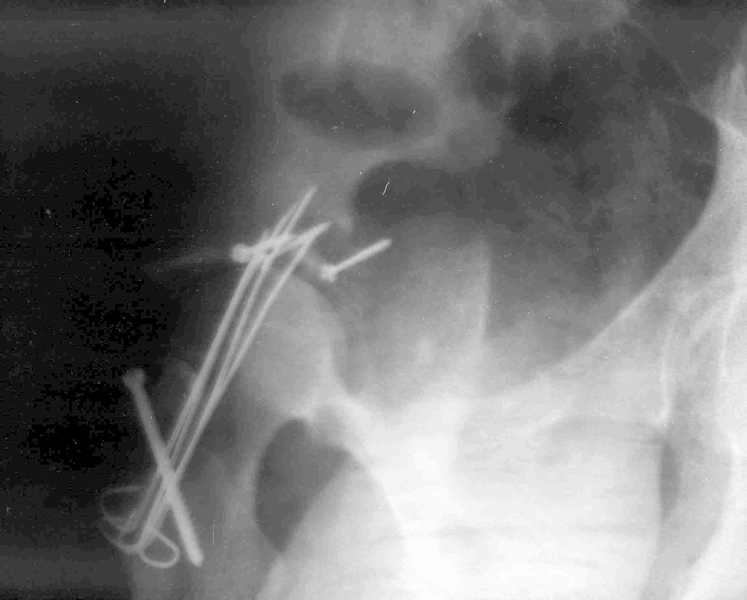

Xray2

Высылаю прямой обзорный и косой подвзошный снимки, косой запирательный неудовлетворительного качества.